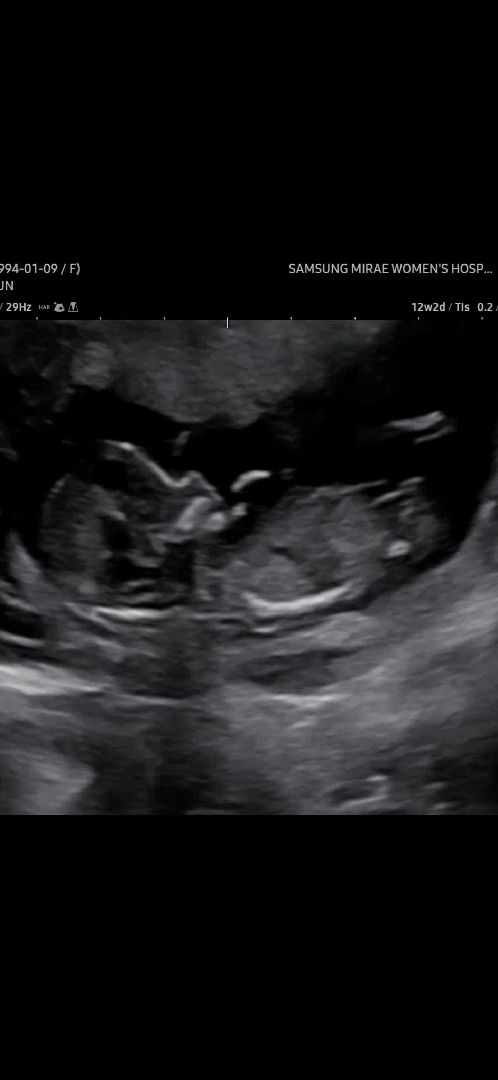

각도법 궁금합니다!

우리 아이는 아들일까요 딸일까요 사진 캡처하기가 힘드네요 ㅠㅠ